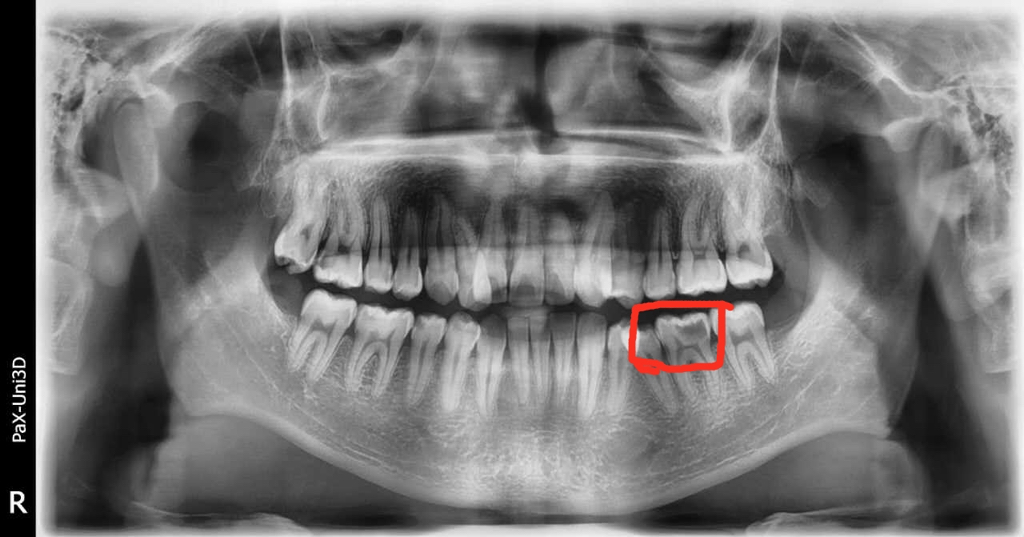

🔎蛀牙

X光拍片为什么要等看牙为什么要拍片?非专业人士如何看懂自己的牙片!_https://www.jmylbn.com_新闻资讯_第9张

△牙齿龋坏比较多,在牙片上会显示黑色阴影的缺损。